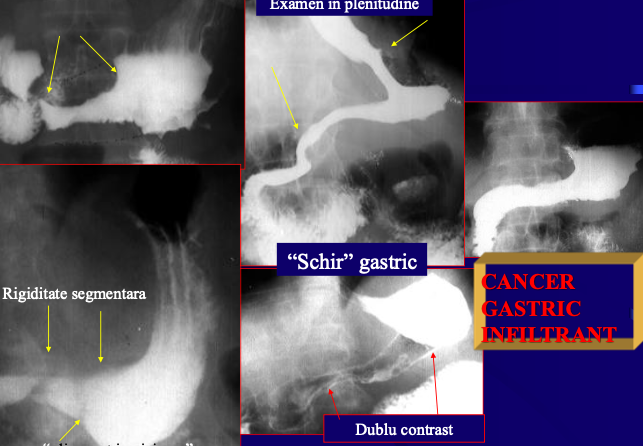

Neoplasm malign gastric infiltrativ